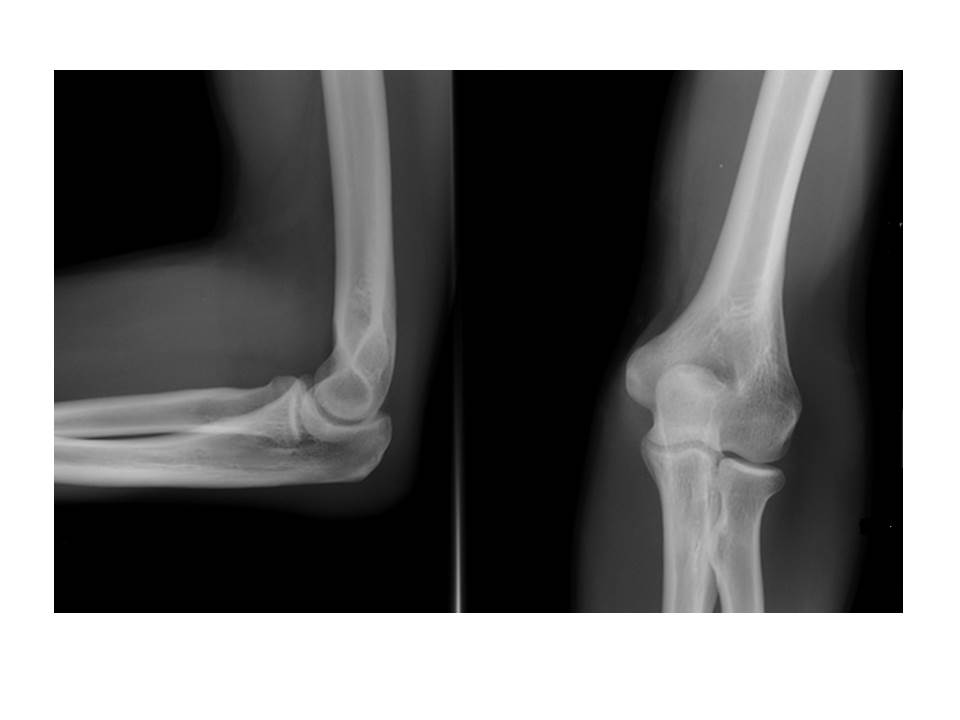

На фото  - рентгенограма ліктьового суглоба: ліворуч - бічна проекція, праворуч - пряма.

Це рентгенограма дорослої людини чи дитини?

Обгрунтуйте свою відповідь. Для цього використайте знання з теми 10 Розділу ІІІ.